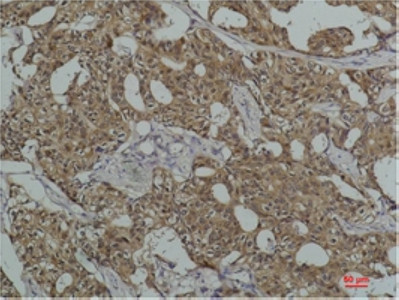

Product information "Anti-HSPA8"

Protein function: Molecular chaperone implicated in a wide variety of cellular processes, including protection of the proteome from stress, folding and transport of newly synthesized polypeptides, activation of proteolysis of misfolded proteins and the formation and dissociation of protein complexes. Plays a pivotal role in the protein quality control system, ensuring the correct folding of proteins, the re-folding of misfolded proteins and controlling the targeting of proteins for subsequent degradation (PubMed:21150129, PubMed:21148293, PubMed:24732912, PubMed:27916661, PubMed:23018488). This is achieved through cycles of ATP binding, ATP hydrolysis and ADP release, mediated by co-chaperones (PubMed:21150129, PubMed:21148293, PubMed:24732912, PubMed:27916661, PubMed:23018488, PubMed:12526792). The co-chaperones have been shown to not only regulate different steps of the ATPase cycle of HSP70, but they also have an individual specificity such that one co-chaperone may promote folding of a substrate while another may promote degradation (PubMed:21150129, PubMed:21148293, PubMed:24732912, PubMed:27916661, PubMed:23018488, PubMed:12526792). The affinity of HSP70 for polypeptides is regulated by its nucleotide bound state. In the ATP-bound form, it has a low affinity for substrate proteins. However, upon hydrolysis of the ATP to ADP, it undergoes a conformational change that increases its affinity for substrate proteins. HSP70 goes through repeated cycles of ATP hydrolysis and nucleotide exchange, which permits cycles of substrate binding and release. The HSP70-associated co-chaperones are of three types: J- domain co-chaperones HSP40s (stimulate ATPase hydrolysis by HSP70), the nucleotide exchange factors (NEF) such as BAG1/2/3 (facilitate conversion of HSP70 from the ADP-bound to the ATP-bound state thereby promoting substrate release), and the TPR domain chaperones such as HOPX and STUB1 (PubMed:24318877, PubMed:27474739, PubMed:24121476, PubMed:26865365). Plays a critical role in mitochondrial import, delivers preproteins to the mitochondrial import receptor TOMM70 (PubMed:12526792). Acts as a repressor of transcriptional activation. Inhibits the transcriptional coactivator activity of CITED1 on Smad- mediated transcription. Component of the PRP19-CDC5L complex that forms an integral part of the spliceosome and is required for activating pre- mRNA splicing. May have a scaffolding role in the spliceosome assembly as it contacts all other components of the core complex. Binds bacterial lipopolysaccharide (LPS) and mediates LPS-induced inflammatory response, including TNF secretion by monocytes (PubMed:10722728, PubMed:11276205). Participates in the ER-associated degradation (ERAD) quality control pathway in conjunction with J domain-containing co-chaperones and the E3 ligase STUB1 (PubMed:23990462). Interacts with VGF-derived peptide TLQP-21 (PubMed:28934328). [The UniProt Consortium]

| Keywords: | Anti-Heat shock cognate 71 kDa protein, Anti-Heat shock 70 kDa protein 8, Anti-Lipopolysaccharide-associated protein 1, Anti-LAP-1, Anti-LPS-associated protein 1, HSPA8 Antibody |

| Antibody Type: | Monoclonal |

| Clone: | 1K21 |

| Species reactivity: | human, rat, mouse |